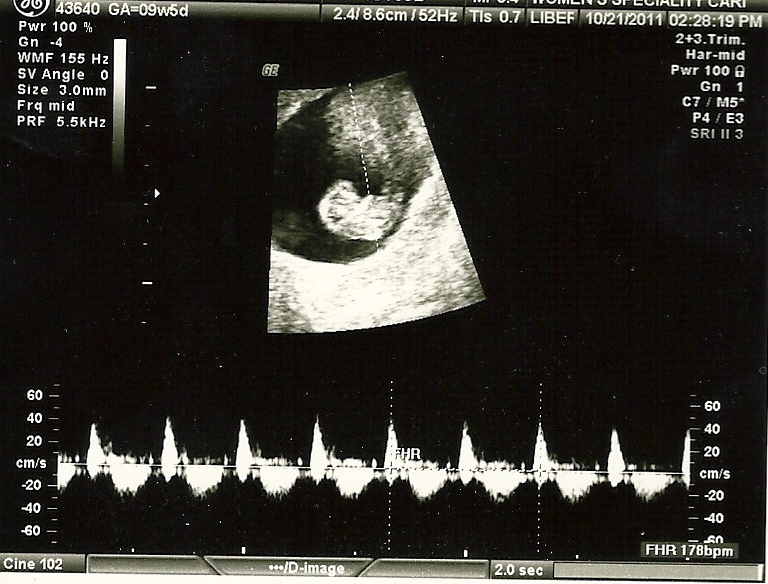

I did not imagine what was to come when they sent me for an ultrasound. I for sure did not think I would see anything remotely human like. I thought maybe a clump of cells or some weird blob inside me maybe. With the rub of the belly, magically a little creature showed up on the screen. I lost it! Where was Patrick?! I assumed The Blob - not a baby! Why didn't I have him come with me?! Then she played the heart beat. The tears and laughter of complete joy just poured from me. This was the best feeling in the world. A feeling I will never forget. Ever.

![]() | |||

| The first day I saw my baby. And heard the heartbeat. |